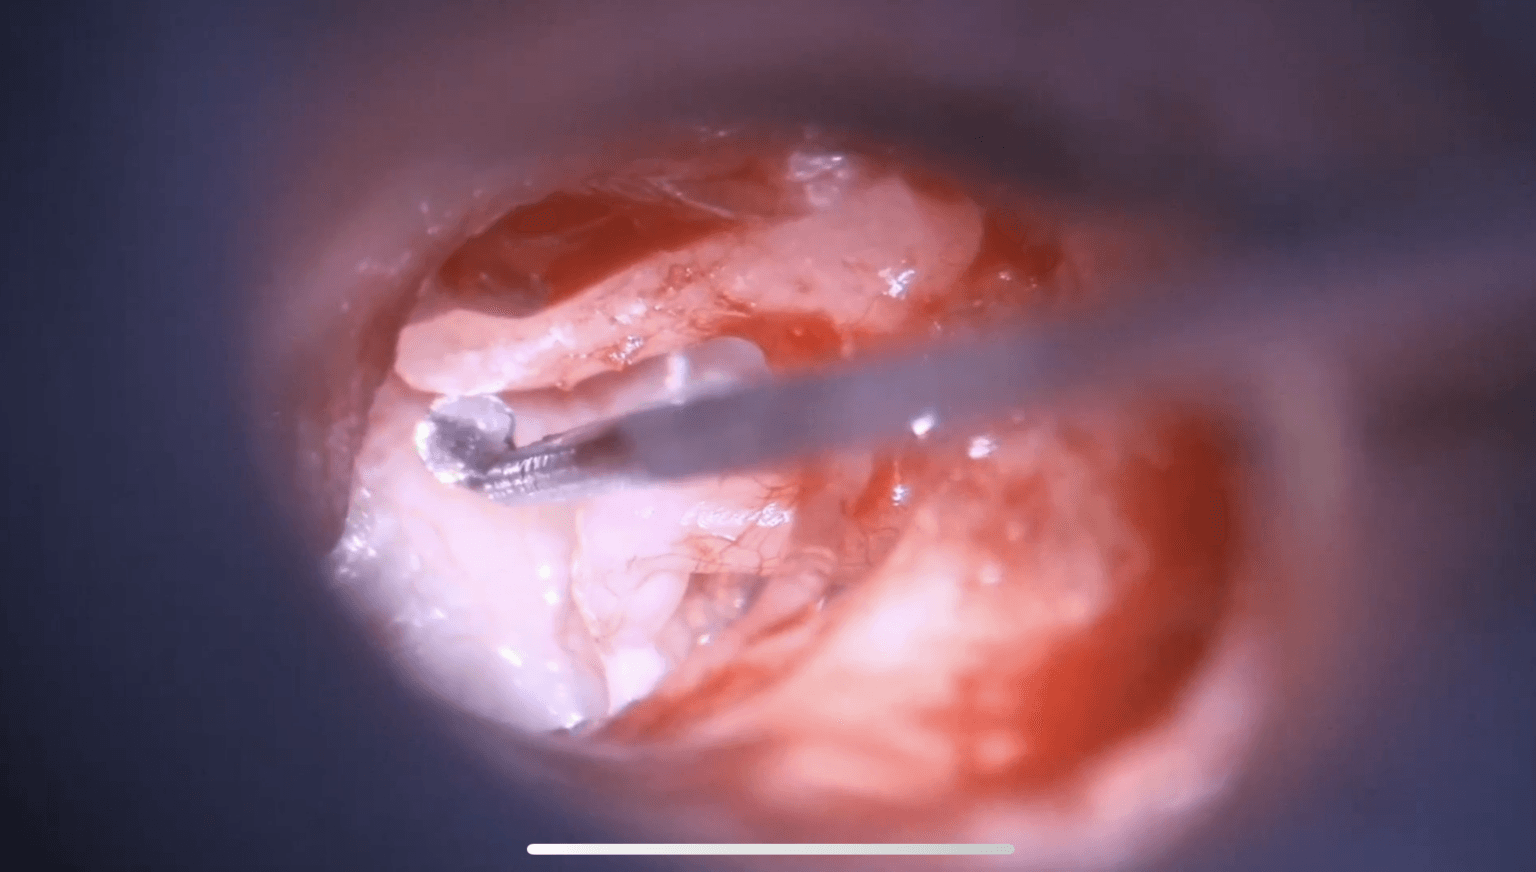

Estapedotomía: ventana oval estrecha y dehiscencia del VII par

El Dr. Robert Vincent realiza una estapedotomía compleja en una ventana oval extremadamente estrecha, asociada a una dehiscencia severa del nervio facial.